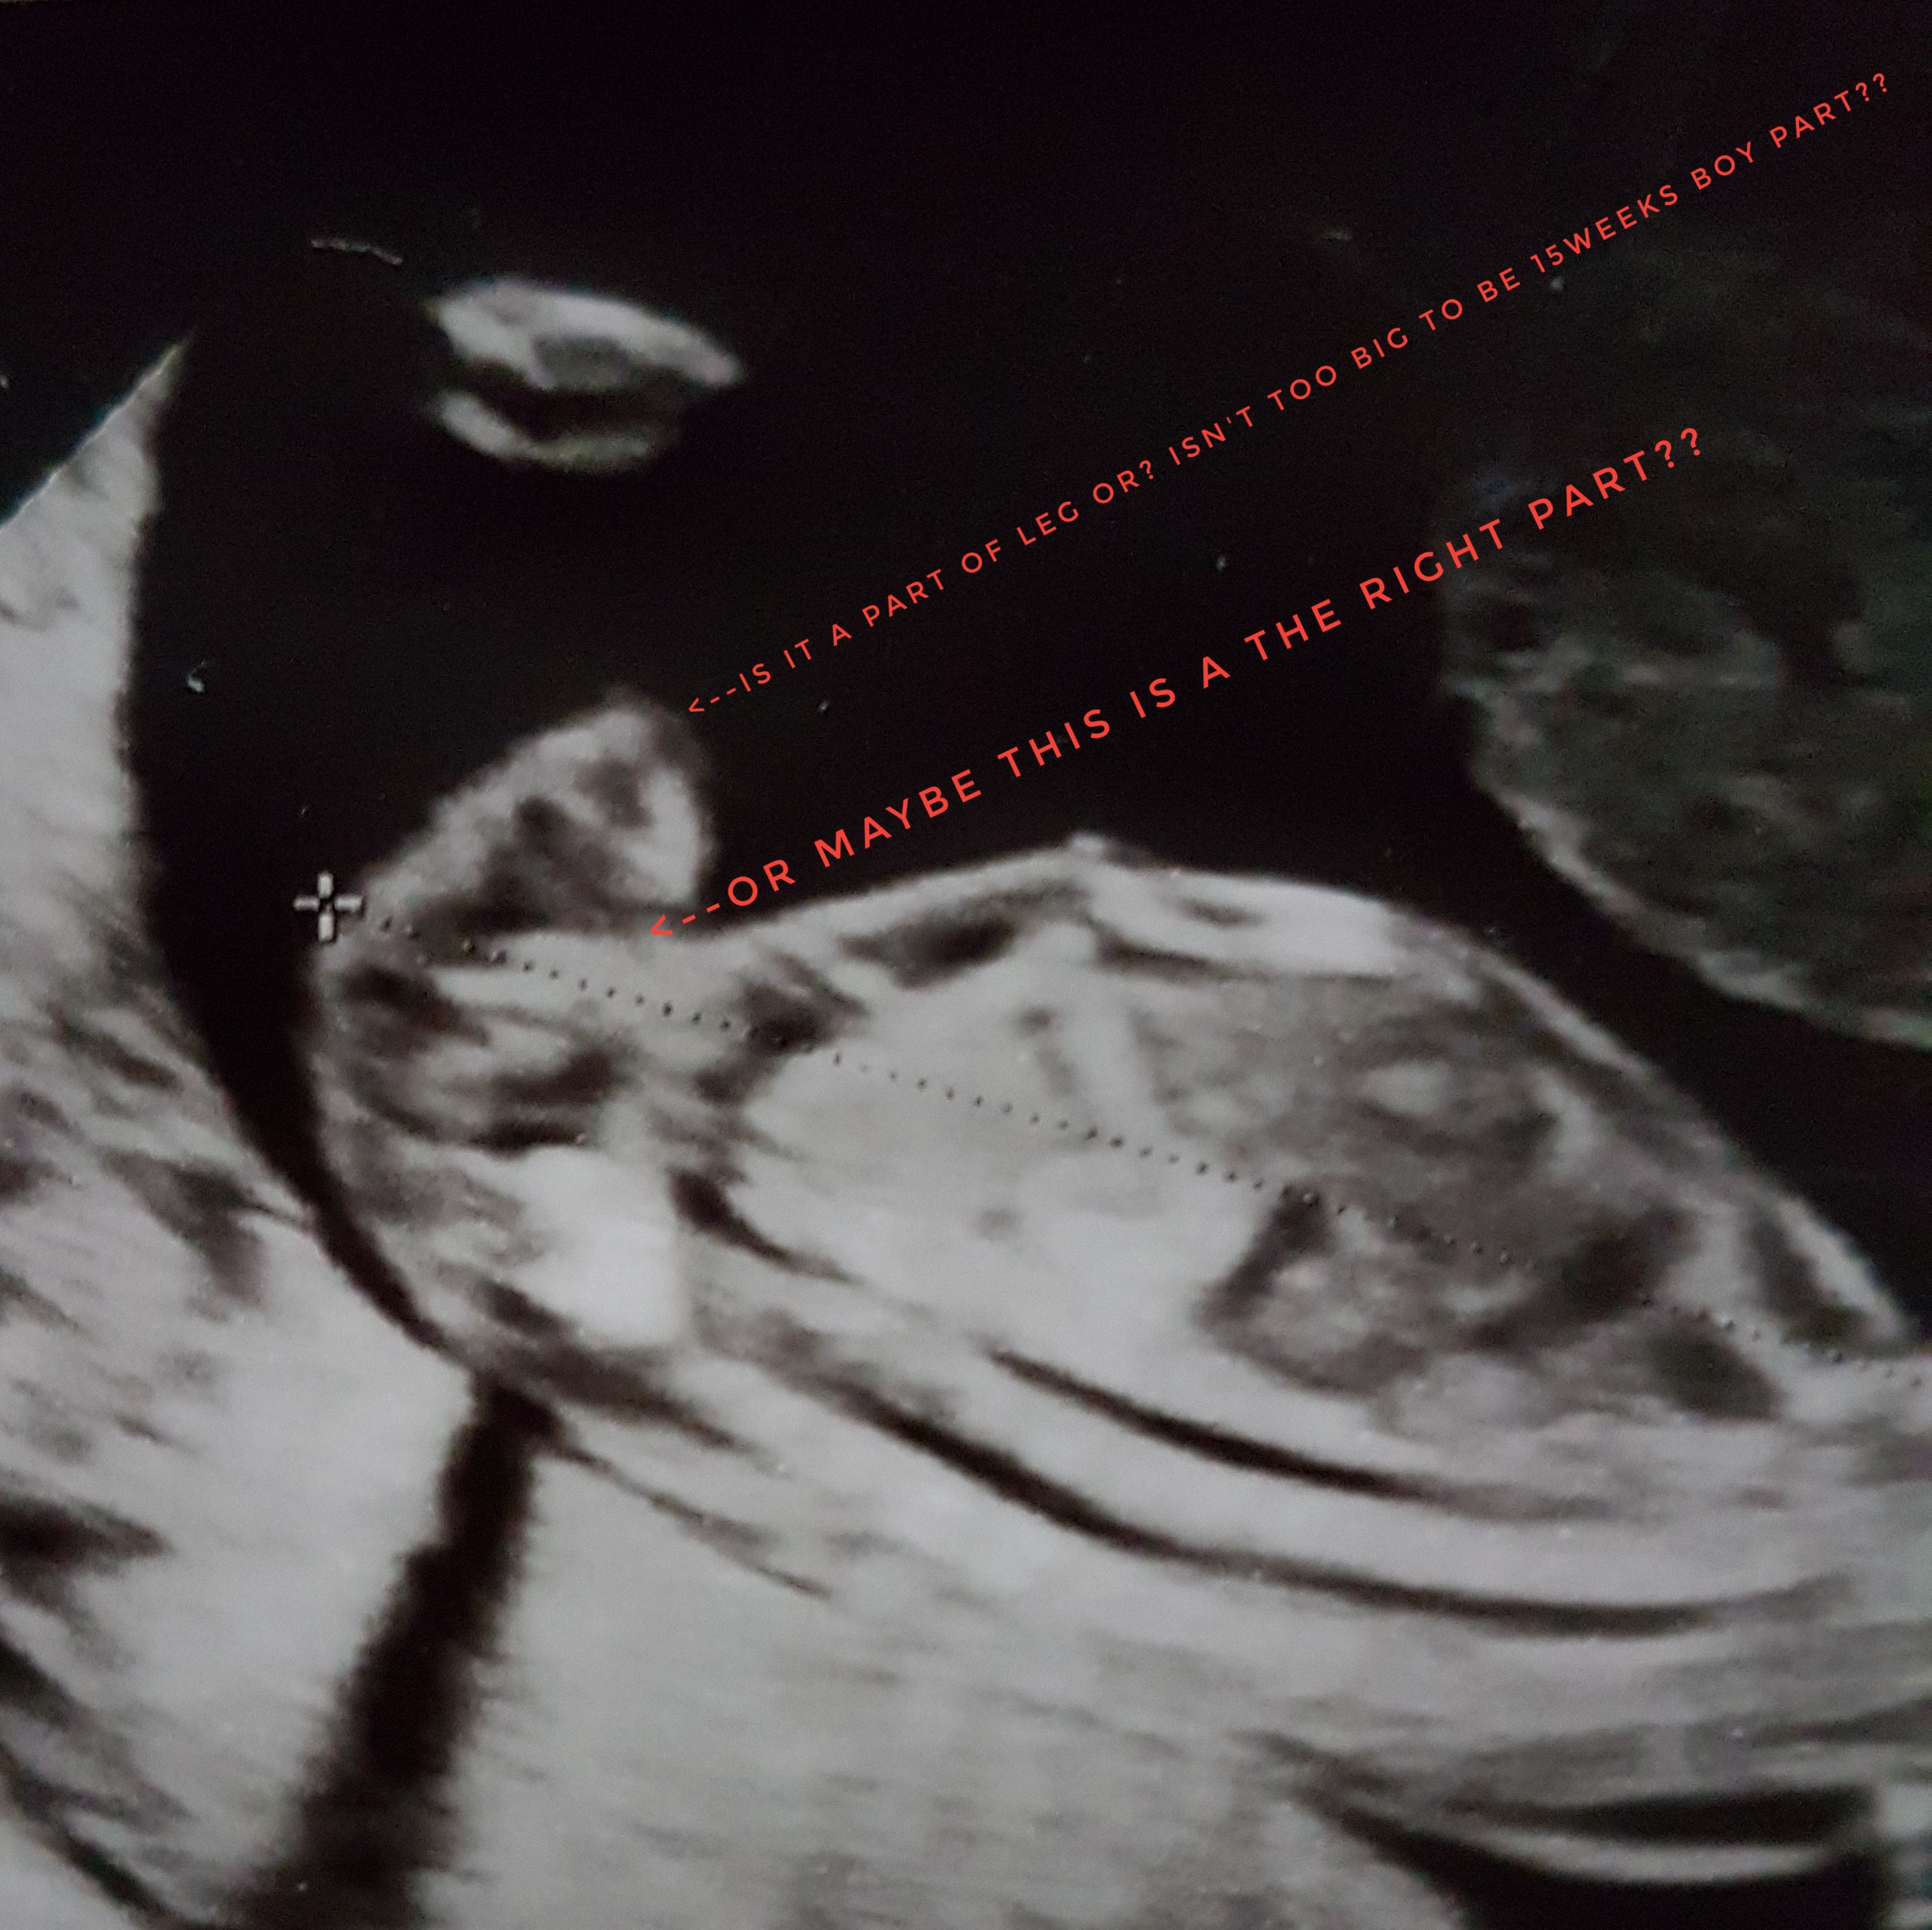

Thank you so much. Please see two another shots from 15 week scan.

Your latest pics changed my mind, I'm going with a boy guess. It looks like a fairly obvious penis and scrotum in your newest pics. I'm sorry, I wish I could tell you otherwise.